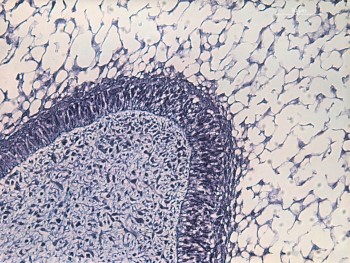

En ellos, según el estadio, podemos identificar como van apareciendo los diferentes componentes del órgano del esmalte que en la fase de campana de el diente multicuspideo (región más a distal de la mandíbula) que podéis observar son: epitelio externo e interno, retículo estrellado, estrato intermedio, así como la papila dentaria en su interior. Hacia cervical se va a constituir la vaina radicular y alrededor se va a diferenciar el saco dentario.

Cuando el germen esta en un estadio mas avanzado de la odontogénesis (más hacia la línea media de la mandíbula) vemos un diente monocuspideo en fase aposicional y por ello en la región cuspídea podemos ver como el epitelio interno se ha diferenciado transformándose en ameloblastos, hay esmalte en formación y en vecindad se observan los primeros odontoblastos y la primera dentina recién formada. Si recorremos el corte hacia la región cervical aún persiste el carácter mas indiferenciado o no secretor.